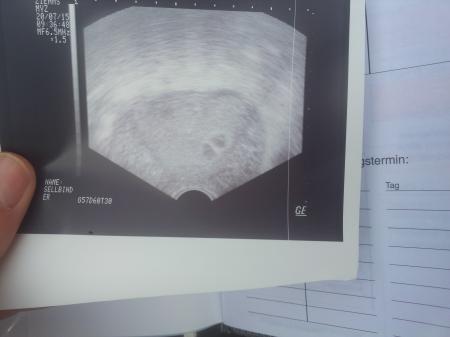

Hallo =) Ich hatte am Montag endlich nen Frauenarzt Termin und ja wie auf dem Bild zu sehen ist werden es wahrscheinlich Zwillinge..... Meine Schwester meinte so sah es bei ihr auch aus und dann wurde es doch nur ein Baby.... Ich werde sie trotzdem behalten ganz klar aber Zwillinge war immer meine größte Angst habe Angst das ich das nicht schaffe....wem von euch hatte es auch schon mal den Anschein das es zwei werden und wurde dann doch nur eins? Oder wer hat schon Zwillinge? War es sehr anstrengend? Mein großer war als Baby schon anstrengend und dann zwei von seiner Sorte wird sehr schwer Liebe grüße Bela

Bild zu Kann mir jemand die Angst nehmen? - Schwanger - wer noch? Rund um die Schwangerschaft